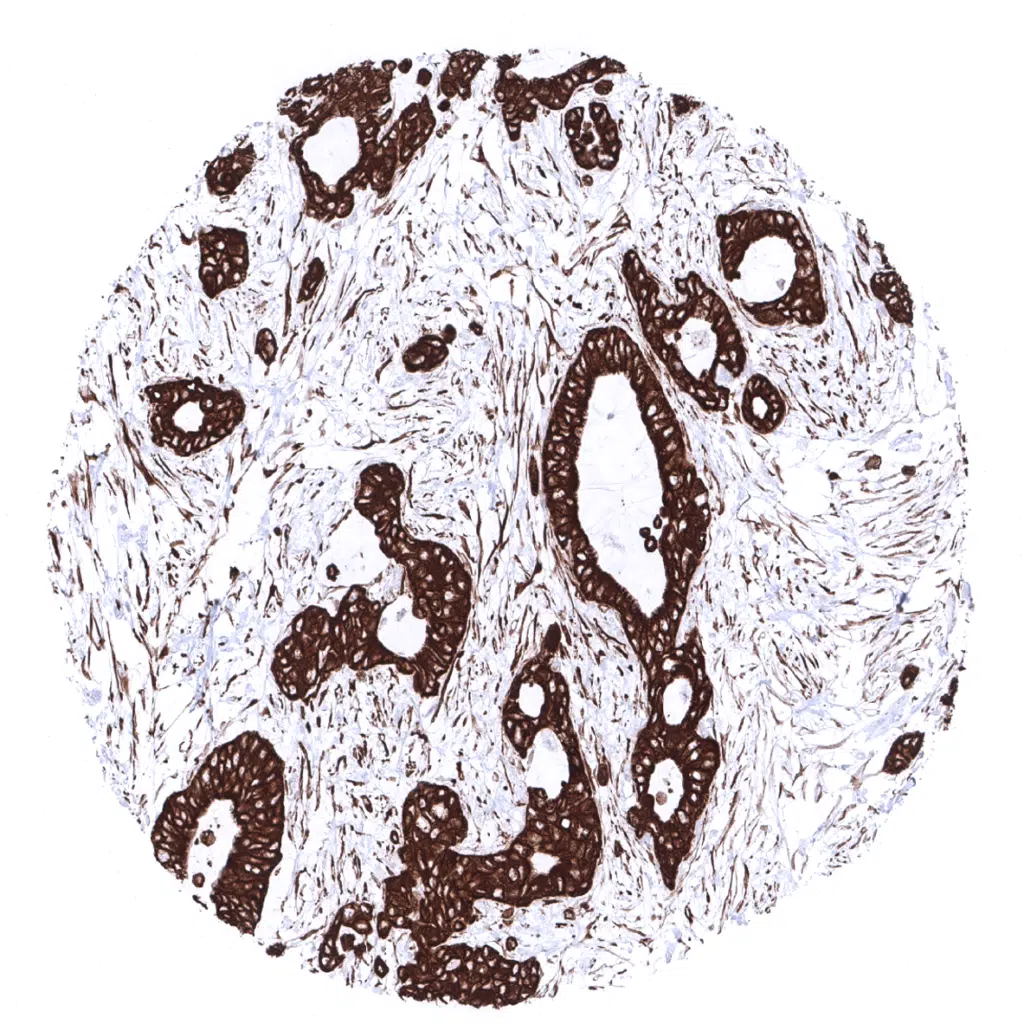

Strong pan Cytokeratin immunostaining in a poorly differentiated adenocarcinoma of the colon.